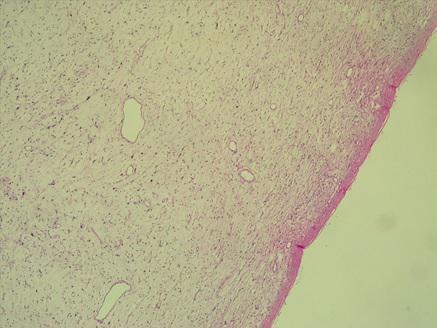

*Case 6 : Dr KOBENAN Rebecca

email: kobrebecca@gmail.com

Clinical detail: 54-year-old man with a brain abscess.

Please, consult the virtual slides of Case 6 below.